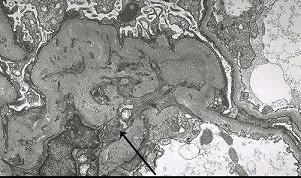

问题 通过阅读下列四张病理片(图-1 PAS染色,图-2 PAM染色, 图-3免疫荧光IgG和补体C3呈颗粒状和团块状沉积——毛细血管壁和系膜区, 图-4电镜下如箭头所示左下方的一个系膜细胞的细胞浆插入了基底膜,使基底膜分离,形成两层基底膜,这两层基底膜堆积在系膜细胞的胞浆上)。 你诊断哪种病理类型 ( )

选项 A.局灶性节段性硬化 B.系膜增生性肾小球肾炎 C.膜性肾病 D.膜增生性肾小球性肾炎Ⅰ型 E.膜增生性肾小球性肾炎Ⅱ型

答案 D